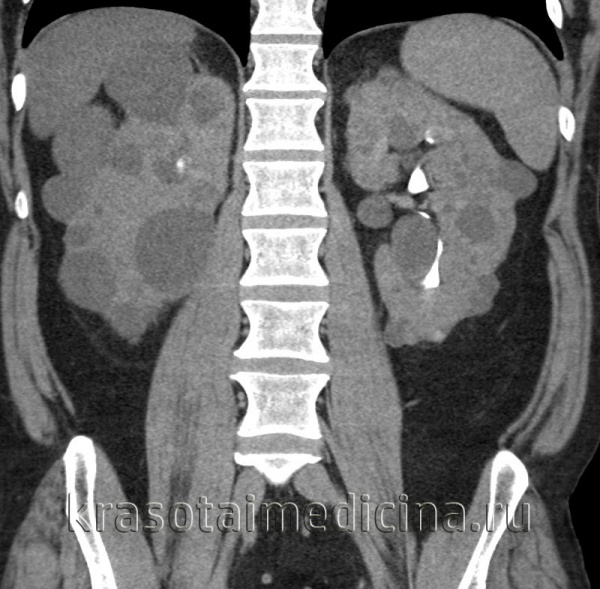

Рисунок 4 | Корональная КТ во время почечной экскреторной фазы демонстрирует заметное увеличение обеих почек за счет бесчисленных кист, а также многочисленные кисты печени.